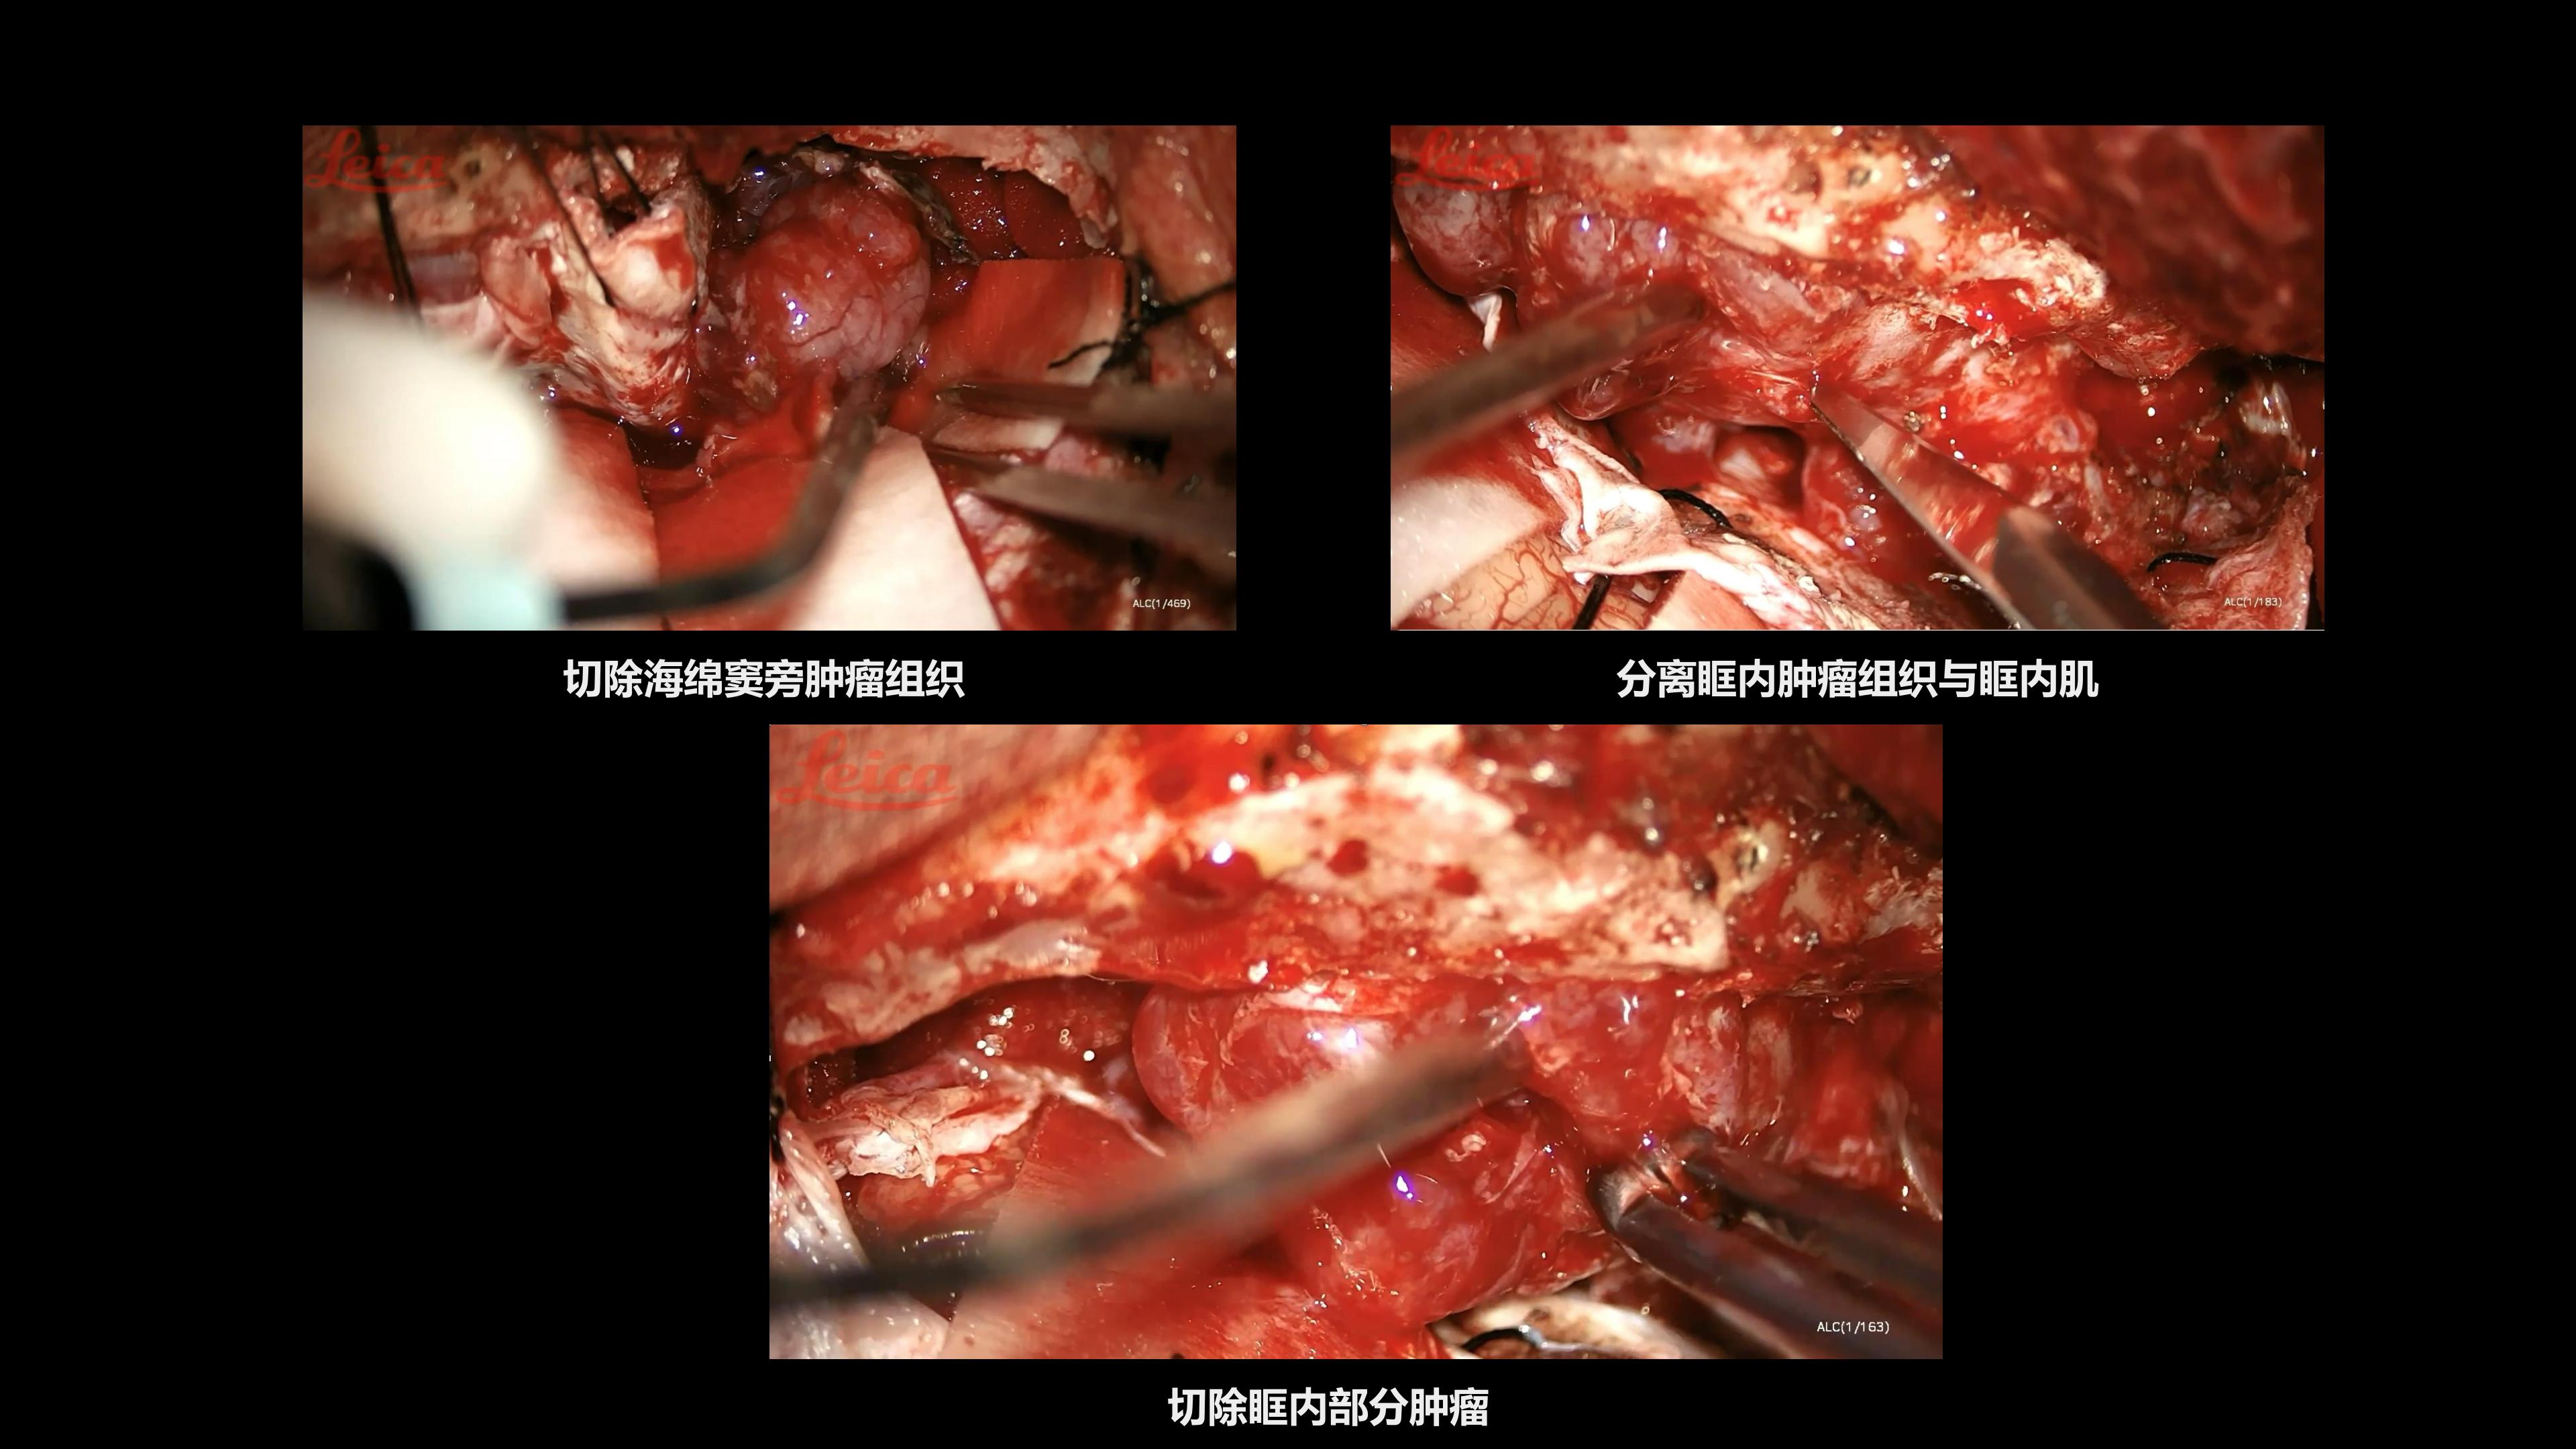

陈保东教授手术作品-右眶内及海绵窦旁孤立性纤维瘤